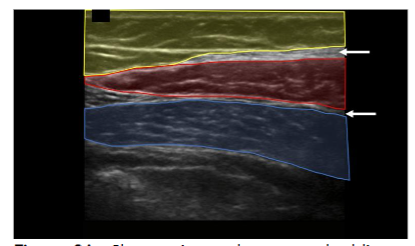

We therefore describe the use of high-frequency (4–13 MHz) interventional ultrasound to directly visualize tissue layers while performing manual adipose tissue harvest for orthobiologic applications. The anterior abdominal wall is widely considered an optimal donor site. Regions containing adipose in the anterior abdomen can be divided into visceral and subcutaneous compartments. The subcutaneous adipose can be further separated into the apical, mantle, and deep layers. High-frequency ultrasound (4–13 MHz) provides real-time visualization of tissue layers, enabling clinicians to localize adipose-rich zones and guide cannula placement while avoiding neurovascular structures.

The layers of the abdomen can be evaluated from superficial to deep: the epidermis and dermis appear thin and hyperechoic; the adipose layer presents as hypoechoic and lobular with hyperechoic fibrous septa. Deep to the adipose layer, muscle appears relatively hypoechoic, separated by fine hyperechoic perimysium, while the bowel wall appears relatively hyperechoic with a hypoechoic lumen and is easily identified by its movement while the patient is at rest.

A “safe zone” for harvest can be defined as the area between the superficial apical layer and the deeper aponeurosis of the abdominal musculature in the upper abdomen, and Scarpa’s fascia in the lower abdomen. Depth markings on the ultrasound screen allow for measurement of the harvest field size. Dynamic scanning can help identify abdominal wall defects or hernias, while Color Doppler is used to locate vascular structures. A linear transducer provides superior resolution at shallow depths, whereas a curved transducer may be selected for larger body habitus or when a wider field of view is preferred. This approach enhances targeted harvest and reduces the risk of complications such as hematoma, seroma, or inadvertent injury to deeper structures.

Once the tumescent technique was complete, a 13-gauge blunt-tipped lipoaspiration cannula (Gallini Medical, Mantova, Italy) attached to a 20 mL VacLok syringe (Merit Medical Systems, Inc., South Jordan, UT) was inserted using an in-plane technique under real-time ultrasound visualization. The cannula was introduced at an angle of less than 30 degrees to the skin surface. Negative pressure was created by retracting and locking the syringe plunger. Gentle lateral-to-medial and medial-to-lateral sweeping motions were used following the pre-planned trajectories to aspirate adipose tissue while always maintaining visualization of the cannula on ultrasound. If cannula visualization was lost, the ultrasound transducer was moved to reacquire the image rather than moving the cannula blindly. Approximately 5 mL of adipose tissue was harvested bilaterally from the abdomens of three cadavers for a total of six 5 mL collections (30 mL in total). Once aspirated, the tissue samples were sent to a laboratory for analysis.